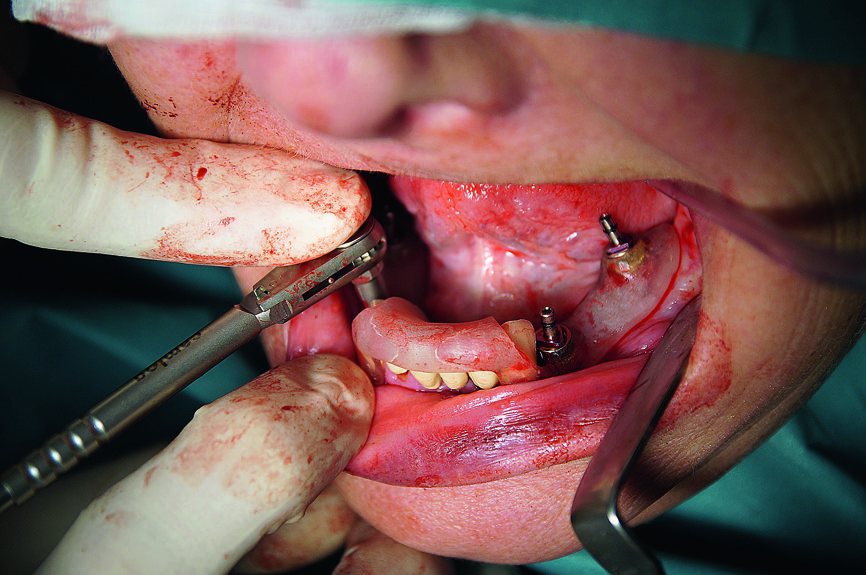

Deux petits lambeaux de pleine épaisseur ont également été décollés afin d’éliminer la vis d’ostéosynthèse utilisée pour stabiliser la greffe osseuse autologue de la chirurgie d’augmentation précédente (Fig. 9). L’insertion des implants a été réalisée à l’aide d’une clé à cliquet DRM et d’une douille standard, avec un couple de serrage prédéfini de 35–45 Ncm, afin de parvenir à une stabilité primaire maximale. Les façonneurs gingivaux ont été insérés avec un couple de serrage de 20 Ncm (Fig. 10) et, après l’insertion des implants, les lambeaux ont été suturés au moyen de fils non résorbables (Prolene 5/0). Les sutures ont été retirées après sept jours. Une tomographie panoramique dentaire postopératoire a permis de visualiser les implants insérés dans la mandibule. Les zones d’augmentation osseuse étaient également clairement reconnaissables sur les deux cotés (Fig. 11).

Fig. 16 : Pose des implants.

Fig. 17 : Insertion manuelle de l’implant CAMLOG au moyen de la clé dynamométrique verrouillée.

Fig. 18 : Tous les implants CAMLOG guidés dans la mandibule.

Dans la mandibule, la muqueuse a été perforée avec un emporte-pièce rotatif au niveau des sites dentaires 36, 34, 32, 42, 44 et 46 (Fig. 14). Après le retrait du gabarit, les endroits de la gencive marques a l’aide de l’emporte-pièce ont été incises davantage et les bouchons de gencive découpée éliminés, afin d’obtenir une mandibule perforée et préparée (Fig. 15). Ensuite, le gabarit de forage a été remis en place. Des forêts à cannelures droites (foret-guide de 6 mm ; forets de mise en forme de 9, 11 et 13 mm) ont été utilisés pour préparer les ostéotomies implantaires au niveau des sites dentaires 36, 34, 32, 42, 44 et 46, conformément aux instructions du fabricant (Fig. 16).

L’insertion des implants a été réalisée à l’aide de la clé à cliquet DRM et de la douille standard, avec un couple de serrage d’environ 35–45 Ncm, afin de parvenir à une stabilité primaire maximale (Fig. 17). Par la suite, les tenons pour navigation implantaire et le guide chirurgical ont été retirés du maxillaire pour y insérer les façonneurs gingivaux, avec un couple de serrage de 25 Ncm (Figs. 18 et 19). Une technique similaire a été utilisée pour la préparation des lits implantaires et l’insertion des implants dans la mandibule, ou six implants CAMLOG de 4,3 mm in diamètre et de 11,0 mm de longueur ont été insérés sous guidage total dans les sites dentaires 15, 14, 12, 22, 24 et 25. Une tomographie panoramique dentaire postopératoire a permis de visualiser les implants insérés dans le maxillaire et la mandibule (Fig. 20).